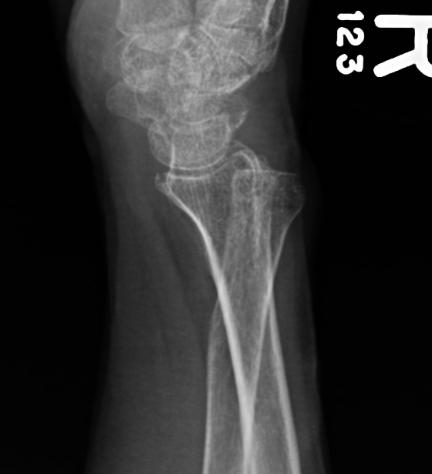

Galeazzi fracture

Galeazzi fracture with DRUJ disruption

Incidence of DRUJ instability after radius ORIF

Rettig et al J Hand Surg Am 2001

- 40 patients with Galeazzi fracture dislocations

- DRUJ instability after radius ORIF

- Type 1: radius fracture < 7.5 cm to articular surface: 55% DRUJ instability

- TYpe II: radius fracture > 7.5 cm to articular surface: 6% DRUJ instability

www.boneschool.com/galeazzi-fracture